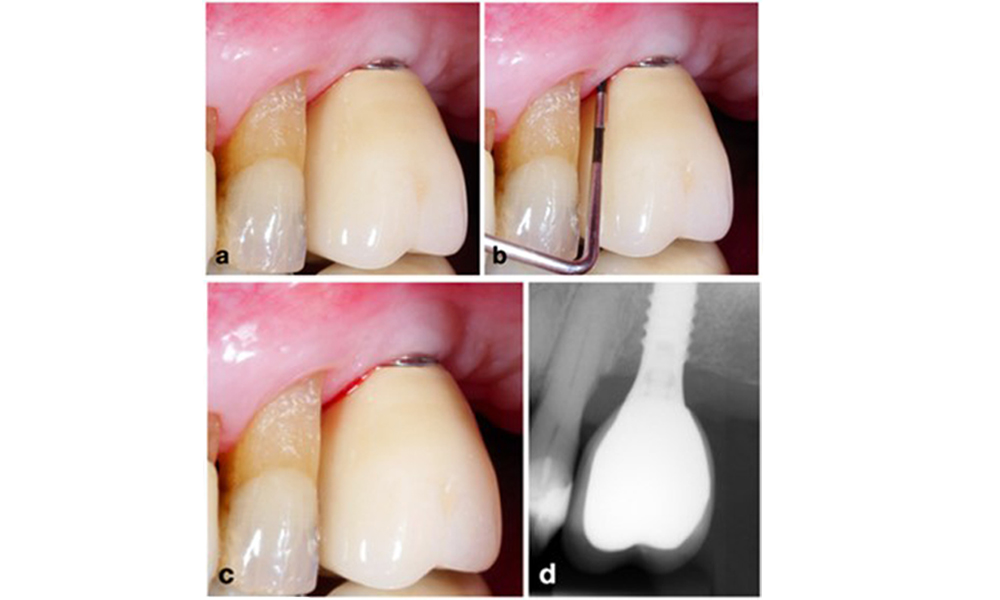

Management of peri-implantitis at implants judged as treatable consists of a non-surgical phase, which is often followed by surgical intervention. For the non-surgical approach, similar measures as those applied for the treatment of peri-implant mucositis are used; based on laboratory experiments air-polishing devices with a subgingival nozzle appear to provide certain advantages in terms of biofilm removal, compared to hand- or ultrasonic instruments (Herrera et al. 2023; Moharrami et al. 2019; Ronay et al. 2017) (figure 9).

Patient case with peri-implantitis. The non-surgical treatment is performed by using the supragingival (a-b) and subgingival handpiece of an air-polishing device (c-d). Removing the supra-construction provides better access to the implant surface (d).

Figure 9. Patient case with peri-implantitis. The non-surgical treatment is performed by using the supragingival (a-b) and subgingival handpiece of an air-polishing device (c-d). Removing the supra-construction provides better access to the implant surface (d).